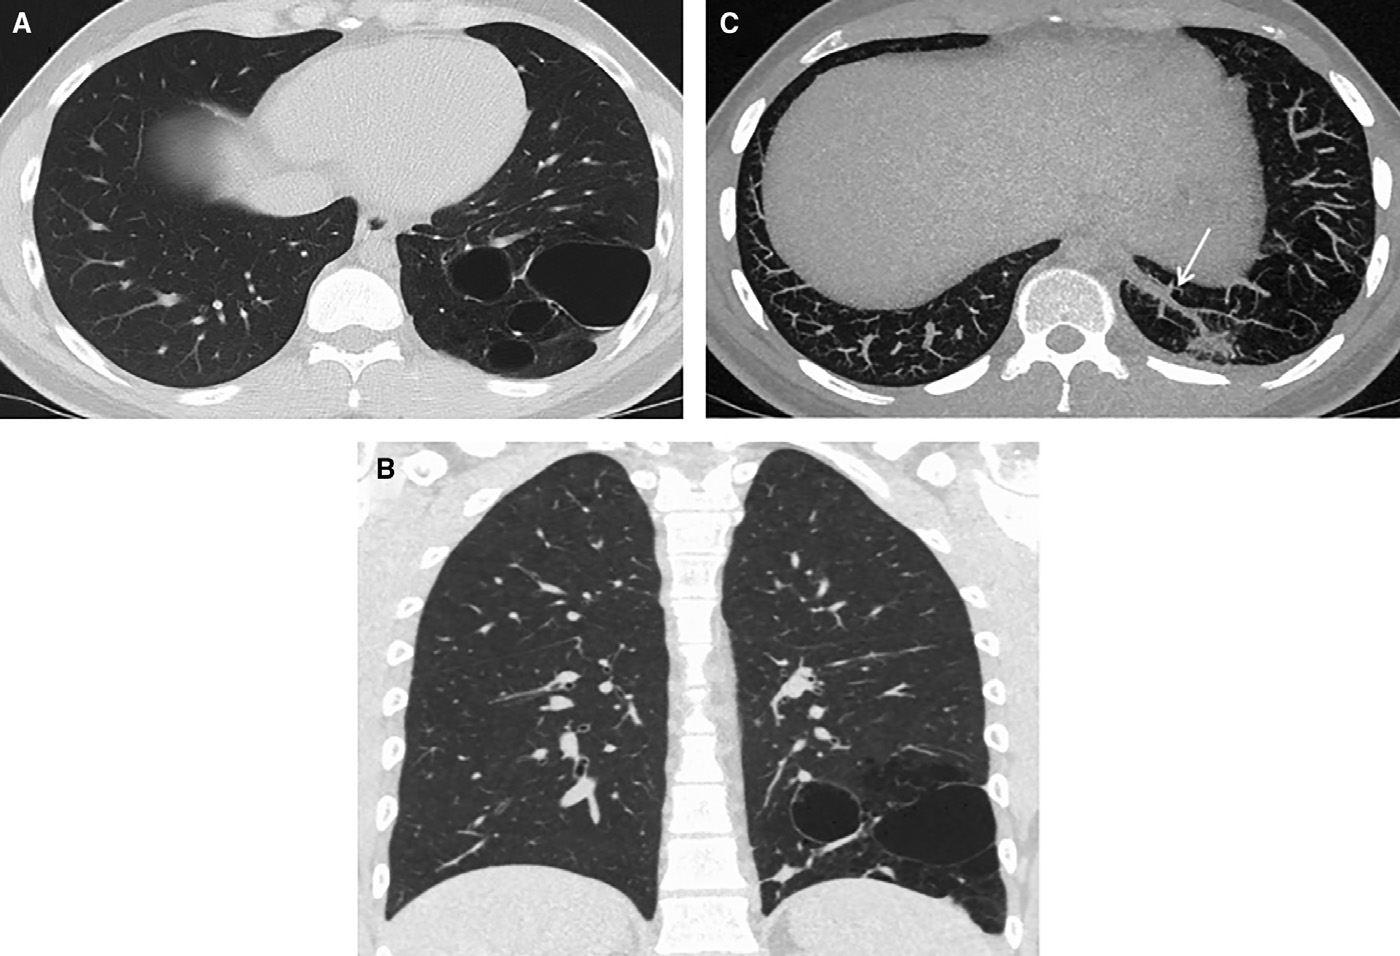

隨訪CT成像顯示左肺下葉基底段存在薄壁和多囊性病變,膈下主動(dòng)脈供血異常(圖4)。多學(xué)科團(tuán)隊(duì)討論后建議行左肺下葉切除術(shù),患者表示接受。切除組織病理學(xué)檢查發(fā)現(xiàn)囊狀擴(kuò)張的氣腔,細(xì)支氣管內(nèi)襯纖毛上皮;無肉芽腫,未見惡性腫瘤證據(jù)(圖5A–5 C)。組織學(xué)表現(xiàn)與1型CPAM一致。鑒于影像學(xué)顯示動(dòng)脈供血異常,患者被診斷為CPAM/BPS混合型病變。

圖4 (A)軸位CT圖像顯示累及左下葉基底部的薄壁、多囊性異常。(B)囊性異常的冠狀位圖像。(C)降主動(dòng)脈的血供異常(實(shí)心箭頭)。